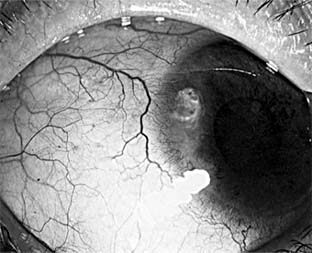

Fungal ulcers are indolent and have a gray infiltrate, often a hypopyon, marked inflammation of the globe, superficial ulceration, and satellite lesions (usually infiltrates at sites distant from the main area of ulceration) (Figure 6-3). The principal lesion-and often the satellite lesions as well-is an endothelial plaque with irregular edges underlying the principal corneal lesions, associated with a severe anterior chamber reaction and a corneal abscess.

Figure 6-3

Figure 6-3: Corneal ulcer caused by Candida albicans.

Most fungal ulcers are caused by opportunists such as Candida, Fusarium, Aspergillus, Penicillium, Cephalosporium, and others. There are no identifying features that help to differentiate one type of fungal ulcer from another.